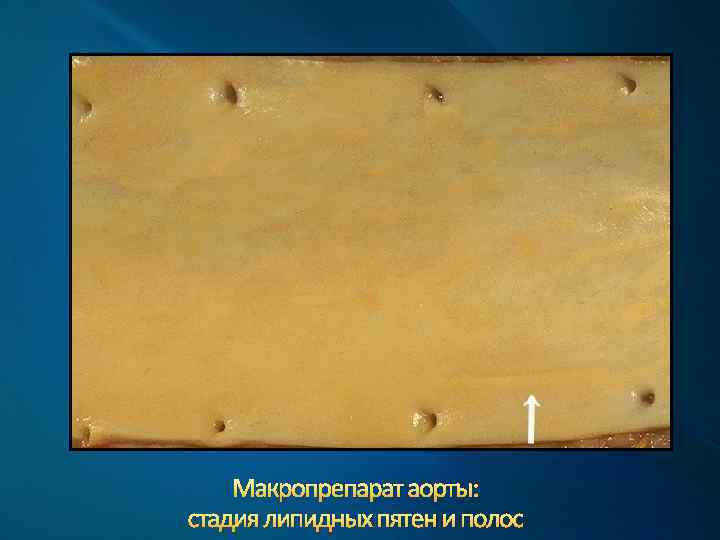

Стадии атеросклероза по макроскопическим критериям 1. Стадия липидных пятен и полос. 2. Стадия фиброзных бляшек. 3. Стадия осложненных поражений. 4. Стадия атерокальциноза.

Макропрепарат аорты: стадия липидных пятен и полос

Макропрепарат аорты: стадия липидных пятен и полос